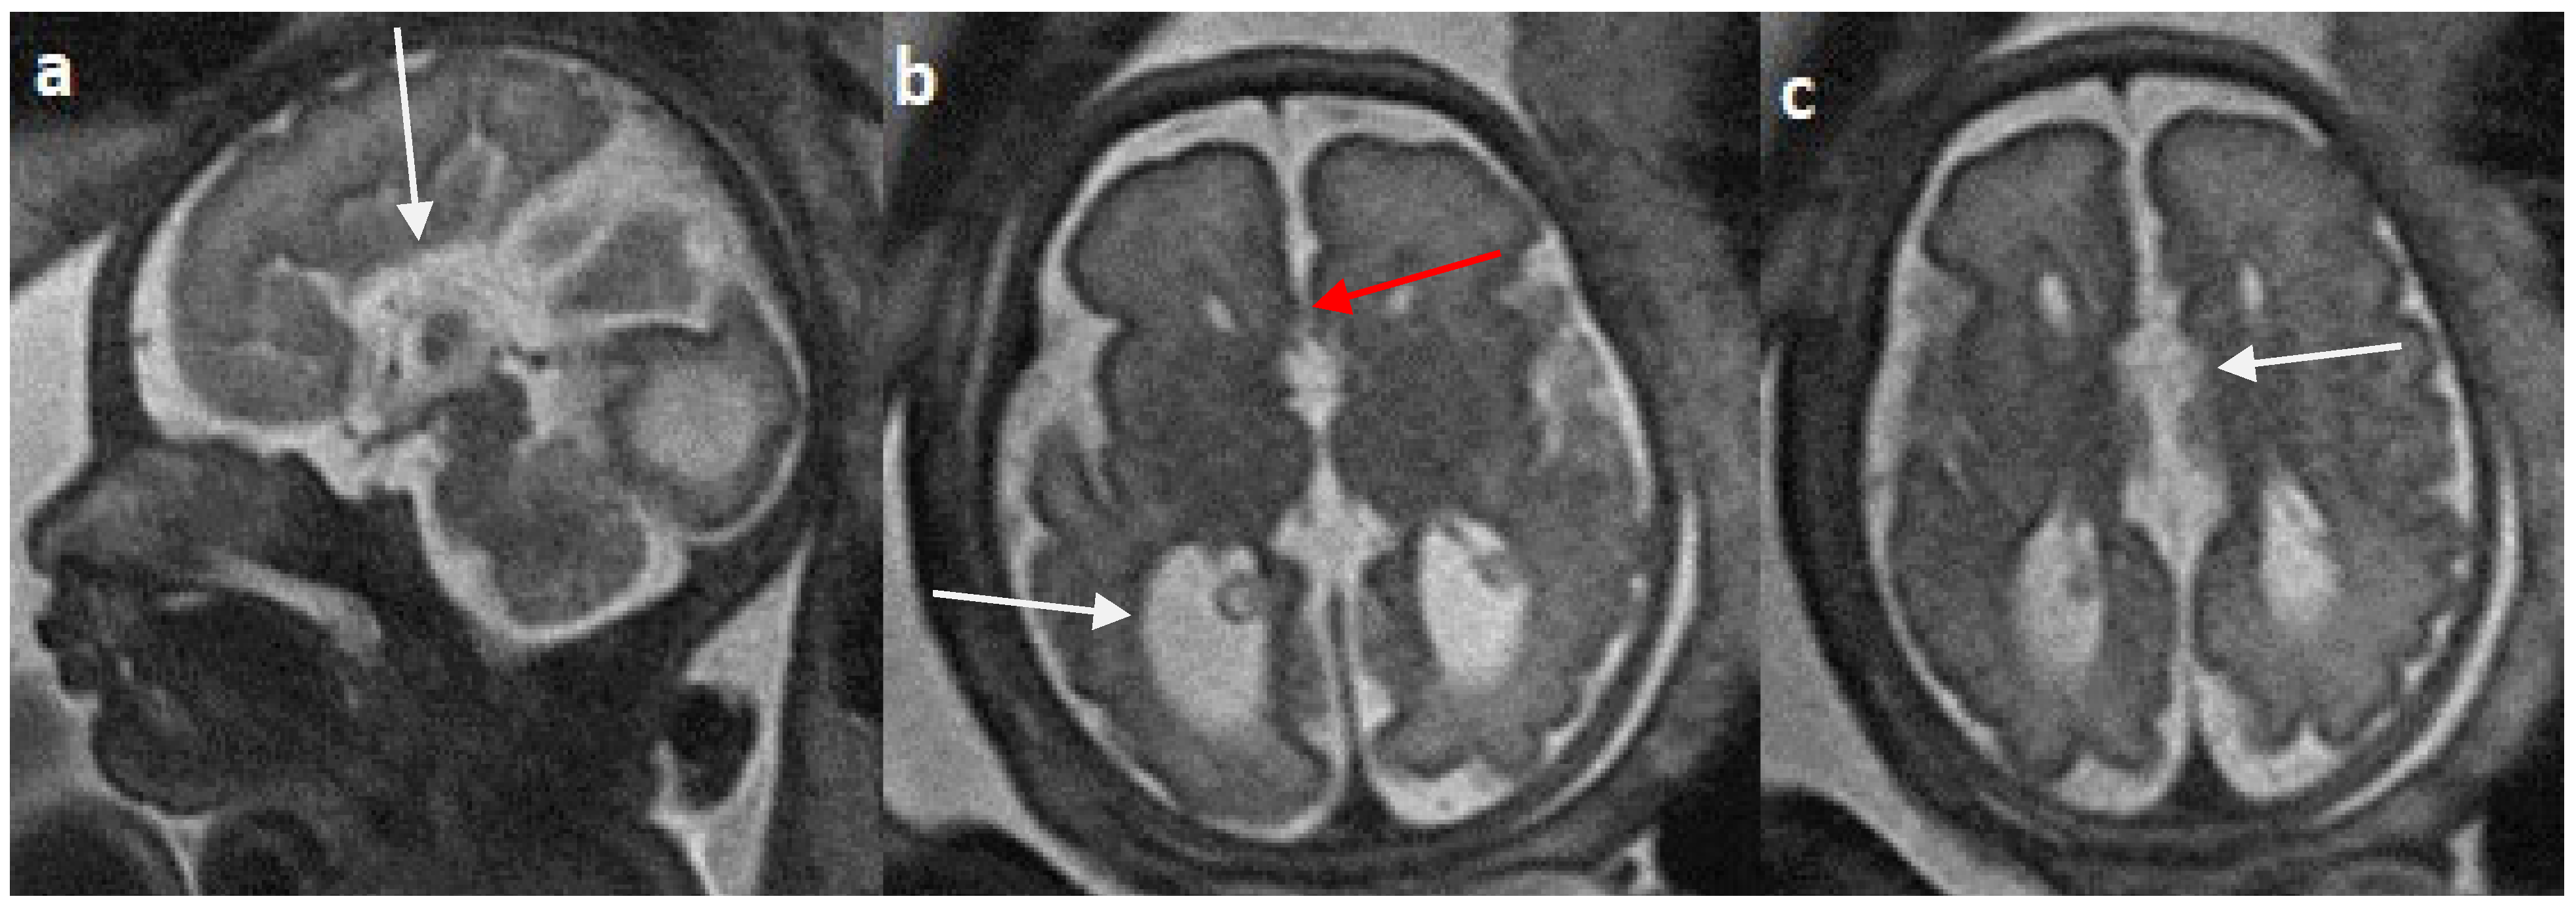

Colpocephaly is seen in 13/24 cases (54%) (Figure 5). Of them, 12 cases had complete agenesis, and one case had hypoplasia. Absent septum pellucidum is seen in 5/24 cases (20.8%) (Figure 6); 4 cases had complete agenesis, and one case had hypoplasia. Probst bundles are identified only in the isolated form of CCA and account for 3/19 cases (15.7%) of complete agenesis and 3/4 cases of the isolated form of CCA (Figure 7). Probst bundles are not seen in other subclasses of CCA. Ventriculomegaly is seen in 7/24 cases with an incidence rate of 0.29%, 5 cases had complete agenesis, and 1 case each had hypoplasia and hypoplasia with dysplasia.

Figure 5.

Fetal MRI images of a 31 gestational weeks aged fetus with complete agenesis of the corpus callosum. (a) A T2-weighted sequence image in sagittal plane shows that the corpus callosum is not visible (white arrow). (b) A T2-weighted sequence image in axial plane shows a “teardrop”-like dilation in the posterior horn of bilateral lateral ventricles suggestive of colpocephaly (white arrow) and absence of corpus callosum and septum pellucidum (red arrow) in the midline. (c) A T2-weighted axial image shows a small interhemispheric fluid collection/cyst in the midline. (arrow). No Probst bundles are observed.

Figure 6.

Fetal MRI images of a 29 gestational weeks aged fetus in a case of hypoplasia with dysplasia of the corpus callosum. (a) A T2-weighted sequence in axial plane showing severe dilatation of the lateral ventricles, particularly at the body and atria, with thinning of the brain parenchyma in the posterior parieto-occipital region, and an associated absent cavum septum pellucidum was noted (white arrow). (b) A T2-weighted sequence in midsagittal plane shows thin anterior corpus callosum with dysplasia. Additionally, hypoplasia of the inferior vermis is noted (white arrow).

Figure 7.

Fetal MRI images of a 20 gestational weeks aged fetus with complete agenesis of the corpus callosum. (a) A T2-weighted sequence image in axial plane showing non-decussating anterior-posterior white matter tracts known as Probst bundles medial to the lateral ventricles (arrow). (b) A T2- weighted sequence coronal image showing Probst bundles indenting superomedial margins of lateral ventricles. Probst bundles are seen with complete agenesis of the corpus callosum.